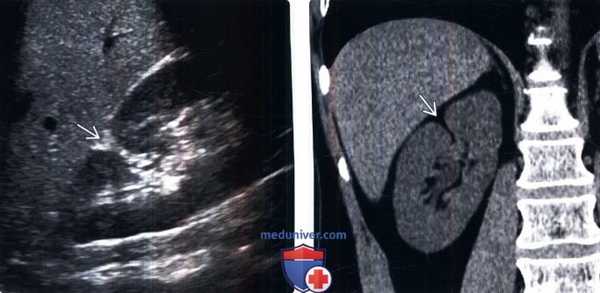

(Слева) УЗИ, косая сагиттальная плоскость сканирования правой почки: у мужчины 55 лет выявлена зона эхогенности треугольной формы на передней поверхности верхнего полюса, продолжающаяся в синус почки, что соответствует дефекту паренхиматозного соединения.

(Справа) КТ, коронарная проекция: у этого же пациента лучше визуализированы жировые углубления и дефект верхнего полюса.